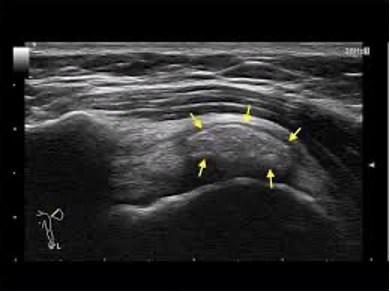

An ultrasound scan is the first tool to get an idea of the problem. The scan detects damaged tissue and inflammatory conditions (fluids).